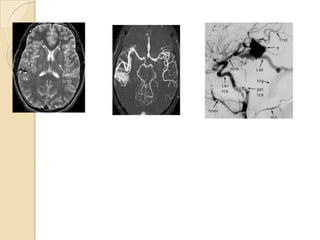

Lt MCA aneurysm

Bilobed aneurysm at Rt MCA bifurcation

3D TOF MRA demonstrates a 6 mm aneurysm arising

from the basilar artery tip and projecting anteriorly

MCA aneurysm seen

InT2W MRI as flow void

In CECT